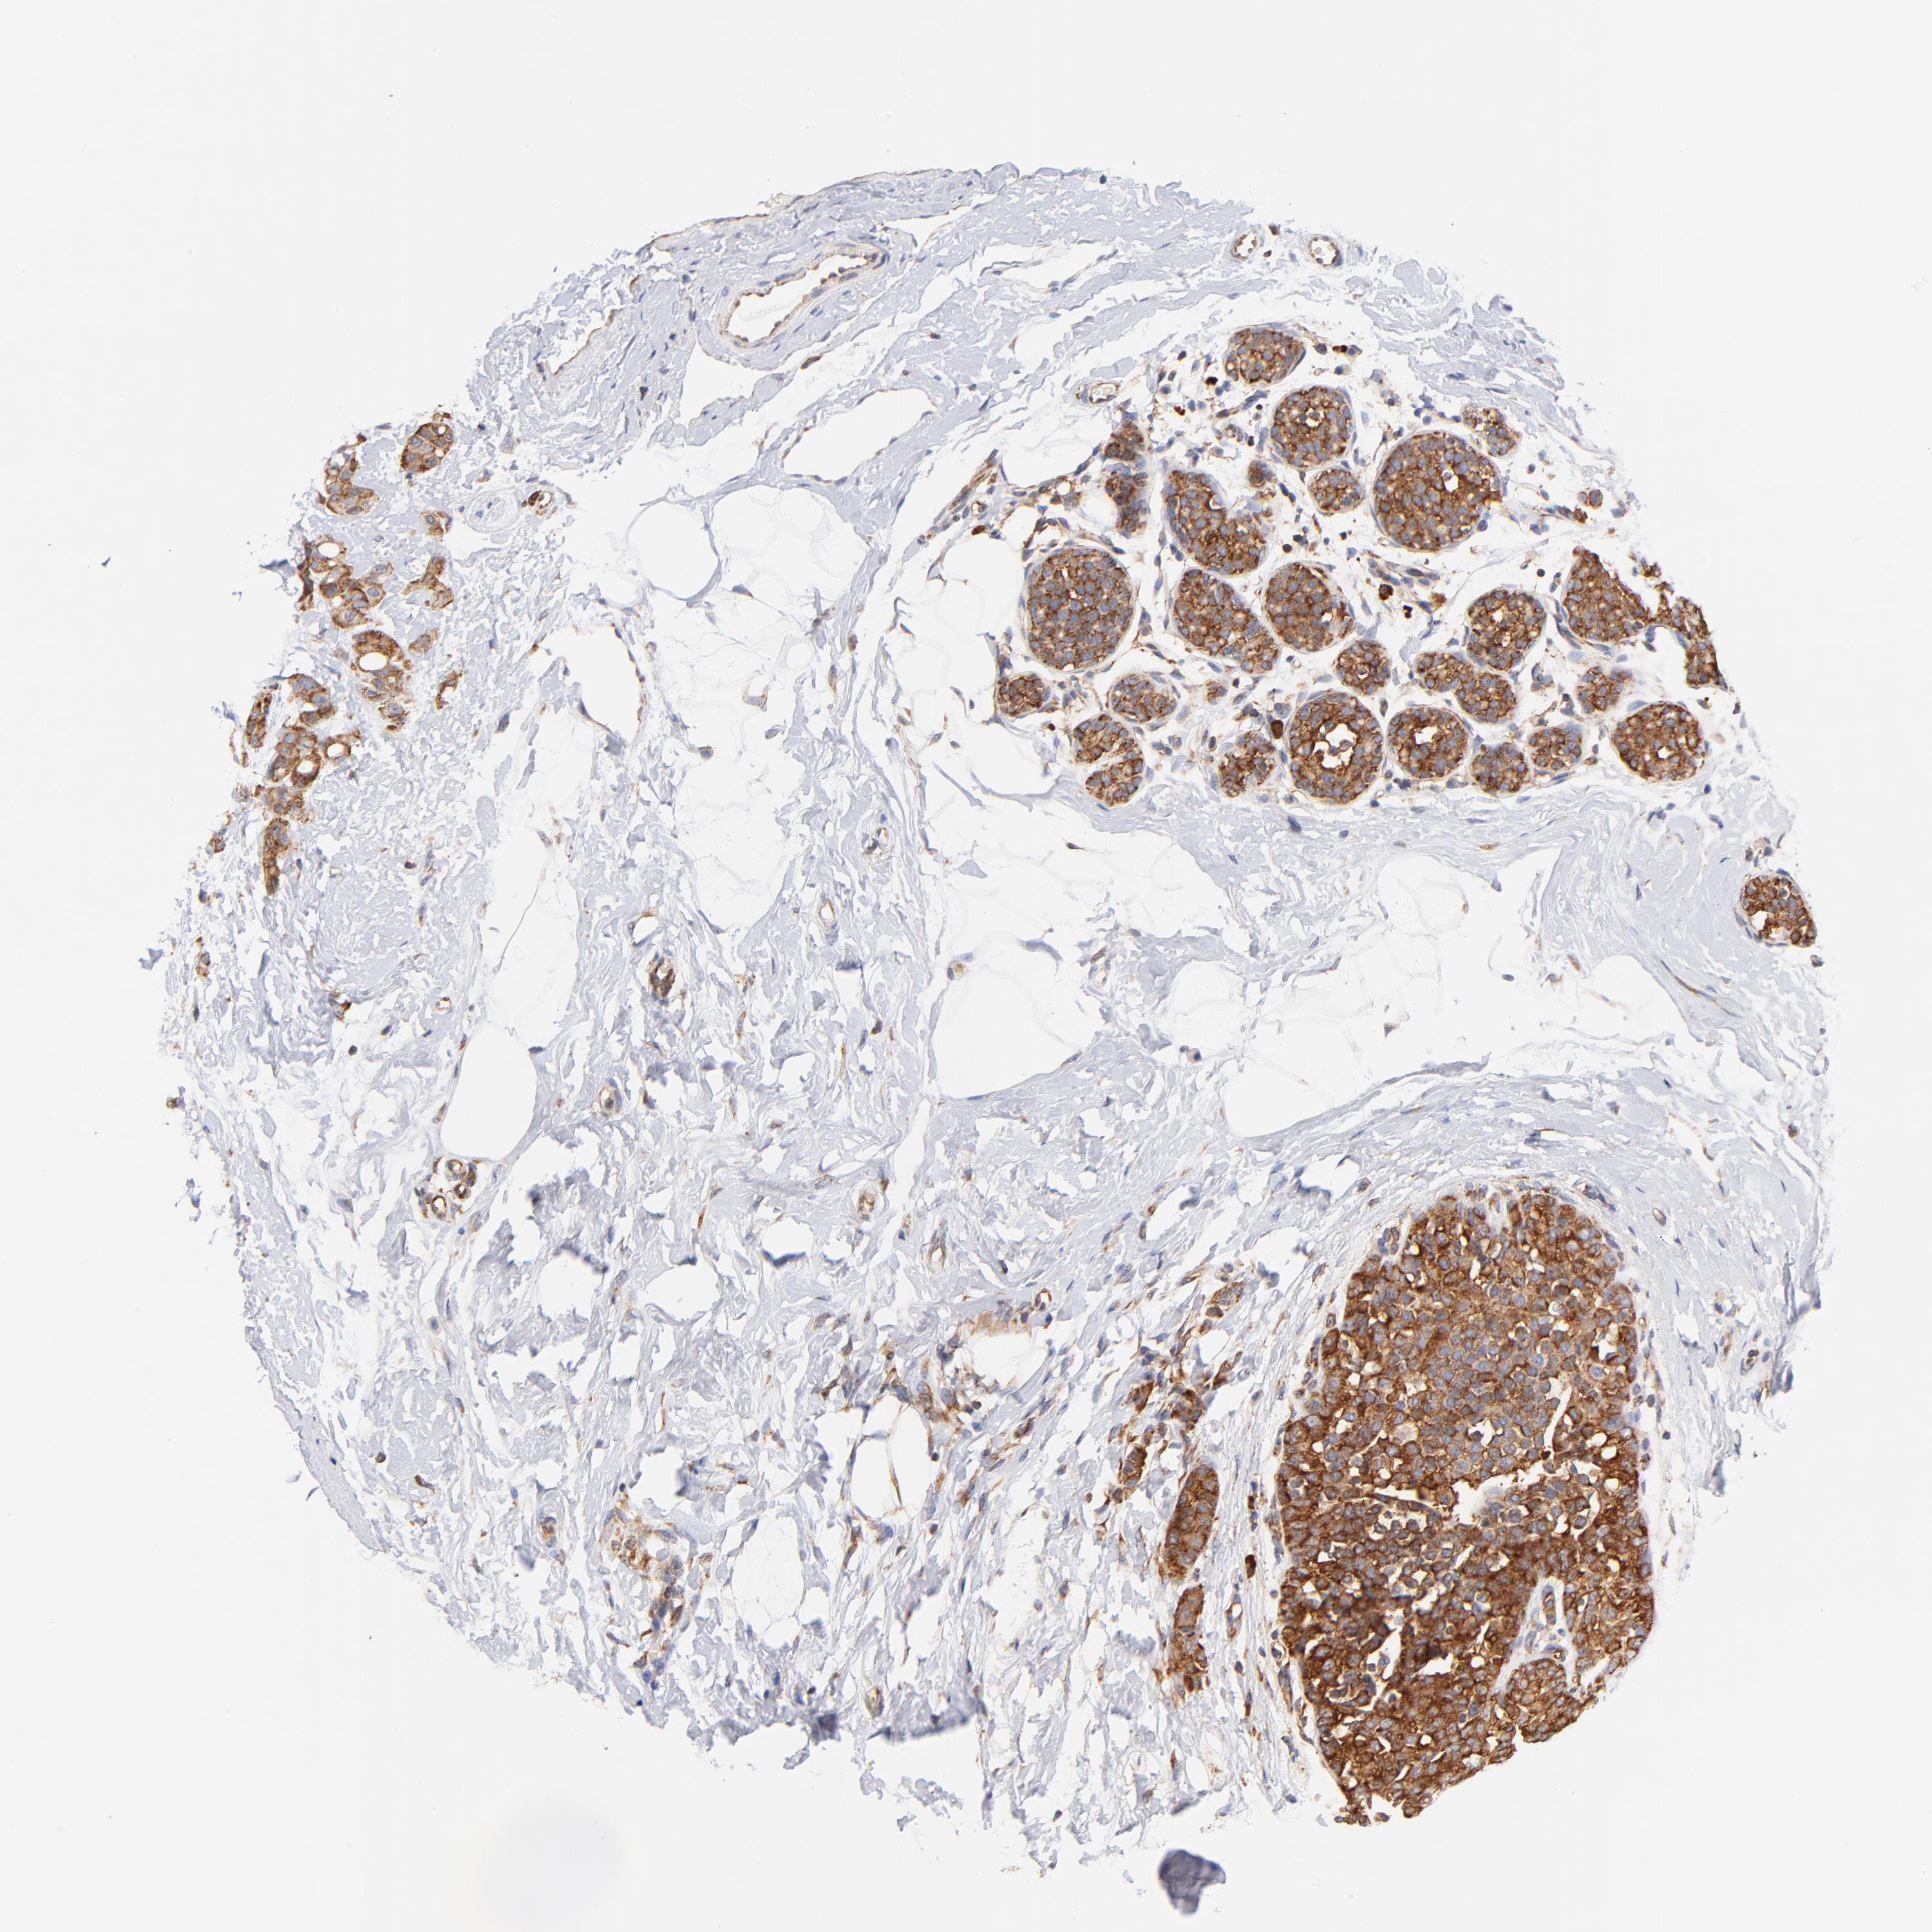

BRCA TCGA BRCA VALIDATION PROTEIN EXPRESSION

Breast cancer

Human cancer